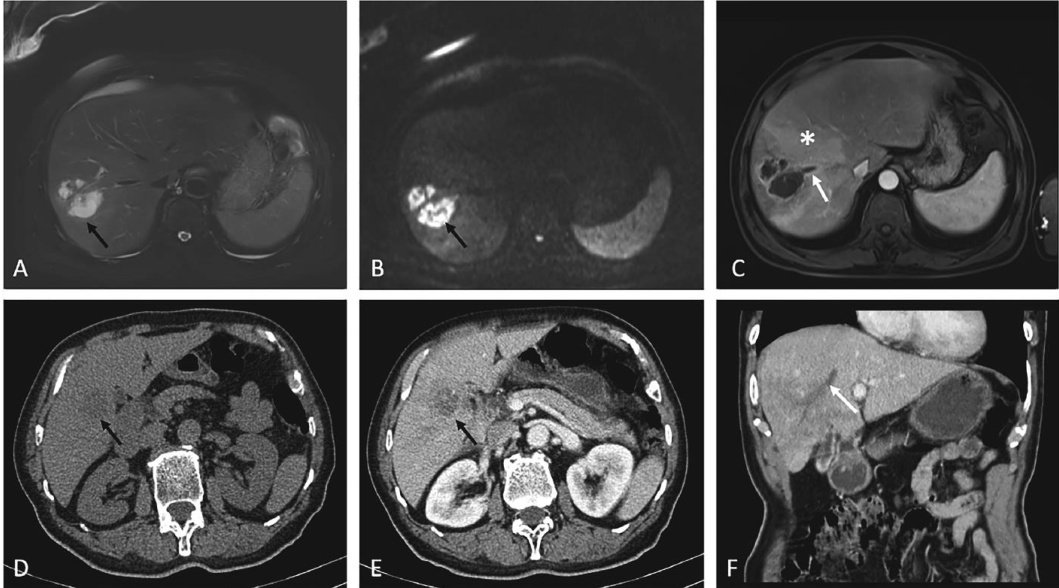

细菌性肝脓肿为临床常见的消化系统感染性疾病,是由细菌等微生物经胆管、门静脉、肝动脉或直接蔓延等途径侵入肝脏引发肝组织局限性化脓性炎症。(剩余6763字)

肝脓肿并发肝脏静脉血栓形成的临床及影像学特征研究